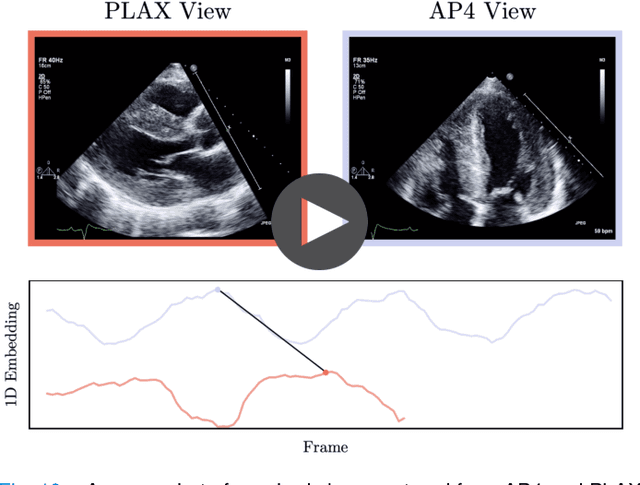

Abstract:In echocardiography (echo), an electrocardiogram (ECG) is conventionally used to temporally align different cardiac views for assessing critical measurements. However, in emergencies or point-of-care situations, acquiring an ECG is often not an option, hence motivating the need for alternative temporal synchronization methods. Here, we propose Echo-SyncNet, a self-supervised learning framework to synchronize various cross-sectional 2D echo series without any external input. The proposed framework takes advantage of both intra-view and inter-view self supervisions. The former relies on spatiotemporal patterns found between the frames of a single echo cine and the latter on the interdependencies between multiple cines. The combined supervisions are used to learn a feature-rich embedding space where multiple echo cines can be temporally synchronized. We evaluate the framework with multiple experiments: 1) Using data from 998 patients, Echo-SyncNet shows promising results for synchronizing Apical 2 chamber and Apical 4 chamber cardiac views; 2) Using data from 3070 patients, our experiments reveal that the learned representations of Echo-SyncNet outperform a supervised deep learning method that is optimized for automatic detection of fine-grained cardiac phase; 3) We show the usefulness of the learned representations in a one-shot learning scenario of cardiac keyframe detection. Without any fine-tuning, keyframes in 1188 validation patient studies are identified by synchronizing them with only one labeled reference study. We do not make any prior assumption about what specific cardiac views are used for training and show that Echo-SyncNet can accurately generalize to views not present in its training set. Project repository: github.com/fatemehtd/Echo-SyncNet.